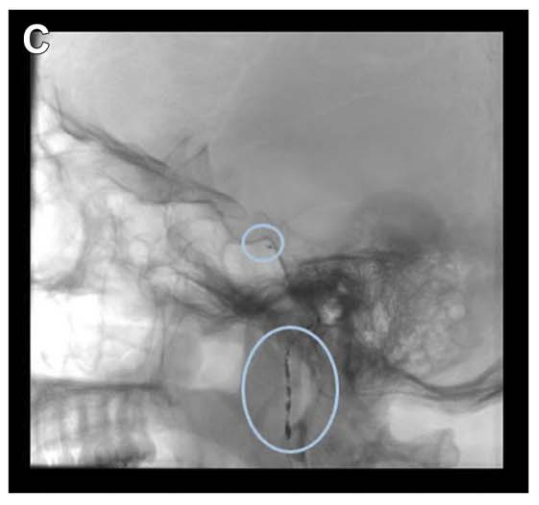

具體分析:由于已知該腫瘤的血供豐富,福教授在手術前進行了DSA檢查,顯示其供血動脈主要為咽升動脈及腦膜垂體干。

諾亞術前栓塞咽升動脈及腦膜垂體干

福教授策略:栓塞可減少出血、軟化腫瘤,便于切除。本例主要供血動脈為咽升動脈的頸靜脈孔支;雖在磨除 JT 后可顯露,但其深而偏外的走行限制早期電凝,故支持術前栓塞指征。為降低后組顱神經損傷風險,選用彈簧圈栓塞。栓塞可減少出血、軟化腫瘤,便于切除。

矢狀位 MRI 顯示腫瘤經栓塞后血供部分阻斷(部分去血管化)。